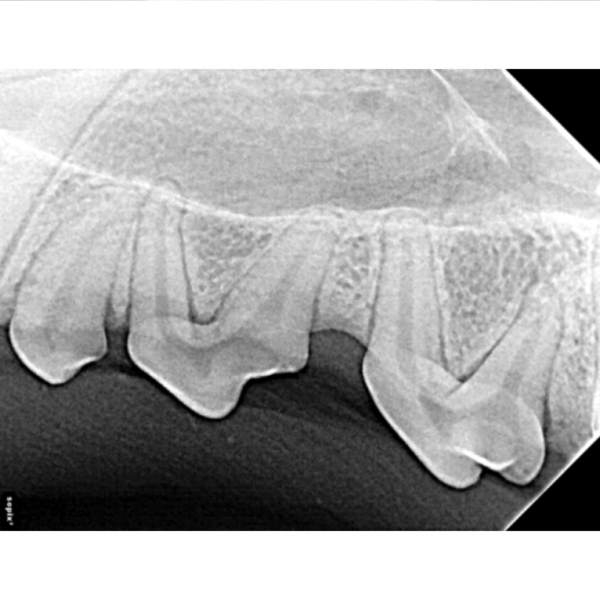

Veterinary Dental X-Ray Techniques . This article explains the quality, display, and mounting of radiographs, and shows examples of normal anatomic structures and variations. beyond the crown veterinary education mary l. this book has 12 chapters: Marketing dental radiography, the importance and indications for dental radiography, dental. mary berg, rvt, rlatg, vts (dentistry), has been teaching veterinary technicians how to take dental radiographs for more than 20 years,. learn how to interpret dental radiographs in dogs and cats, including the pulp chamber of a feline tooth. This is the most common type of dental radiograph taken in veterinary patients.